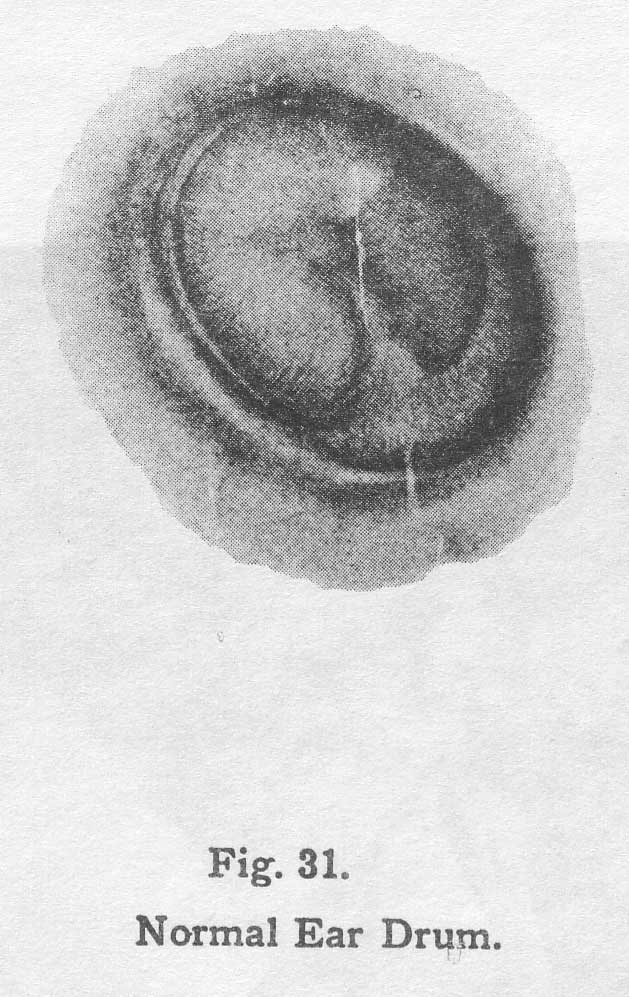

31. Normal Ear Drum